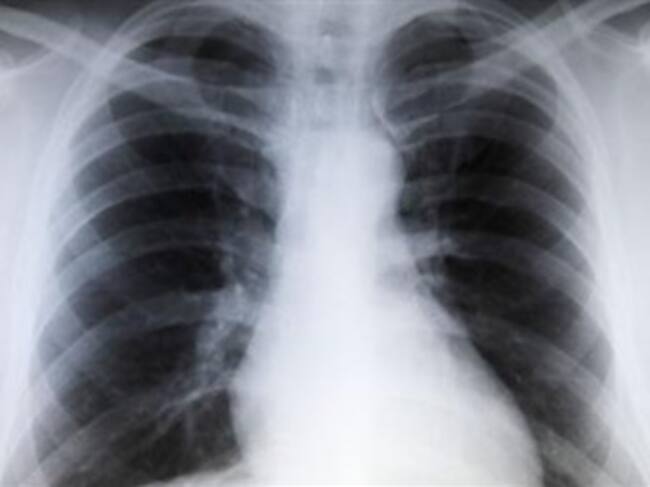

Los perros son capaces de detectar el cáncer de pulmón

Los perros son capaces de detectar el cáncer de pulmón gracias a su fino olfato, según los resultados de un estudio difundido hoy en Austria que abre la posibilidad de salvar vidas mejorando el descubrimiento temprano de la enfermedad